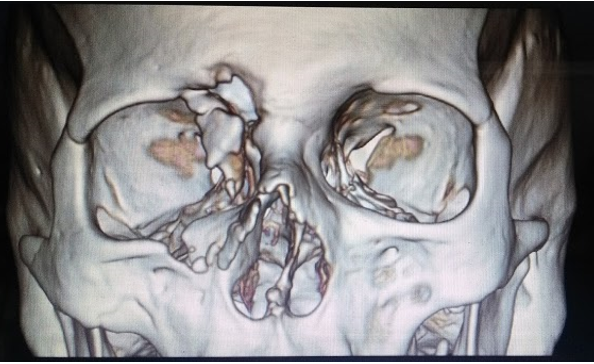

Postoperatorio mediato de 7 días, presenta dehiscencia de puntos de región frontal pero se deciden retirar y permitir cierre por segunda intención. Paciente niega epifora y refiere menos obstrucción nasal.